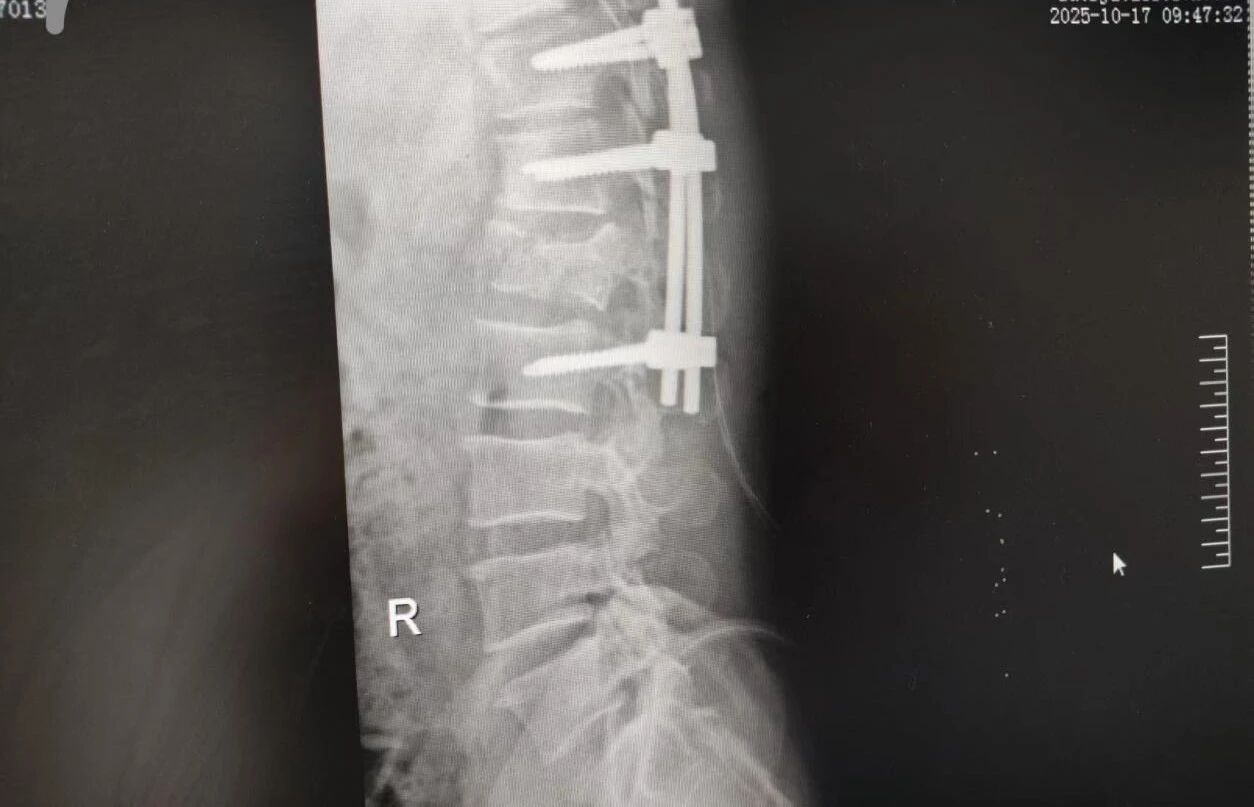

63 歲的王先生(化名)高空作業(yè)時(shí)不慎墜落,由漯河市中醫(yī)院急診科緊急接診。入院時(shí),他已生命垂危,初步檢查結(jié)果觸目驚心:腰 1 椎爆裂性骨折(脊柱嚴(yán)重?fù)p傷,隨時(shí)面臨永久性癱瘓風(fēng)險(xiǎn))、多發(fā)肋骨骨折伴血?dú)庑嘏c肺挫傷(胸腔 “堡壘” 重創(chuàng),呼吸功能幾近崩潰)。任一傷情皆足以致命,多重重創(chuàng)更讓其陷入生死絕境。

針對(duì)腰椎傷情,骨科竇志剛醫(yī)生團(tuán)隊(duì)緊急開(kāi)展腰 1 椎體爆裂性骨折切開(kāi)復(fù)位內(nèi)固定術(shù) + 椎板切除減壓術(shù)。手術(shù)室、麻醉科無(wú)縫銜接開(kāi)通綠色通道,手術(shù)團(tuán)隊(duì)快速就位,術(shù)后患者下肢活動(dòng)恢復(fù)自如。